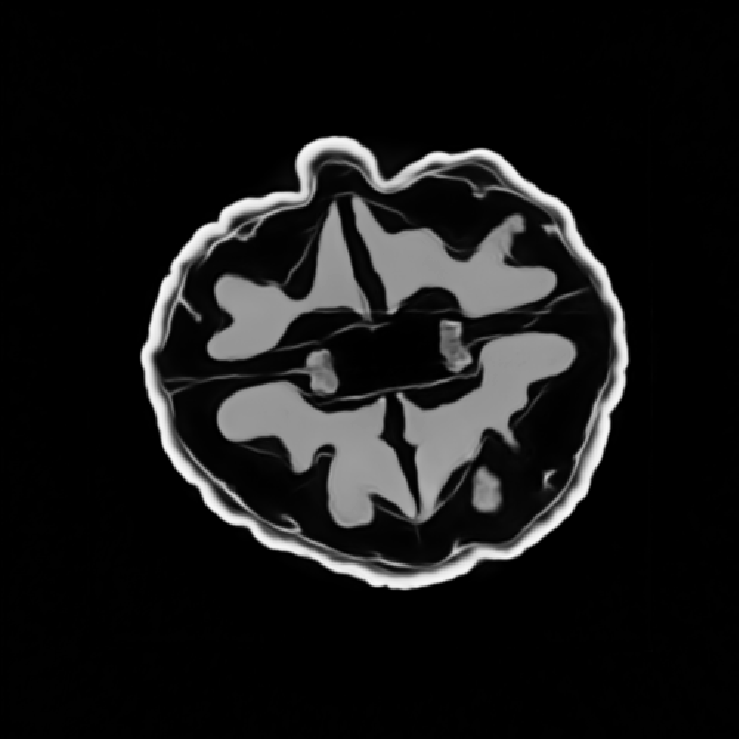

In this work, we find that a good approximation of the normal operator can be obtained by factorizing it as the product of a diagonal matrix and a circulant matrix, which can be efficiently applied using FFTs. This allows us to significantly reduce the computational cost of the data-fidelity step, while maintaining good reconstruction performance. \begin{equation} \label{eq:normal:operator:approximation} \mA^\top \mA \approx \mH = \mathrm{diag}(\vm)^* \mF^{-1} \mathrm{diag}(\bm{\lambda}) \mF \mathrm{diag}(\vm), \end{equation} where $\mF$ and $\mF^{-1}$ are the Fourier and inverse Fourier transforms, respectively, $\vm \in \R^{n}$ is homogeneous to spatial sensitivity map, and $\bm{\lambda} \in \mathbb{C}^{n}$ is the frequency response of the convolution kernel associated with $\mA^\top \mA$.

The parameters $\vm$ and $\bm{\lambda}$ can be learned end-to-end by minimizing the loss \begin{align} \mathcal{L}(\vm, \bm{\lambda}) &= \E_{\rvx \sim \mathcal{N}(\bm{0}, \mI)} \| \mA^\top \mA \rvx - \mH(\vm, \bm{\lambda}) \rvx \|_2^2 \notag\\ &= \| \mA^\top \mA - \mH(\vm, \bm{\lambda}) \|_F^2 \label{eq:frobenius:loss} \end{align}

Illustrations of the normal operator approximation on the Walnut-CBCT dataset. (top row) Original volume slice $\vx$, exact normal operator evaluation $\mA^\top \mA \vx$, and approximated normal operator $\mH\vx$. (bottom row) Learned filter $\bm{\lambda}$, learned mask $\vm$, and squared approximation error $(\mA^\top \mA \vx - \mH \vx)^2$.

Now we can use the approximation $\mH$ instead of the exact normal operator $\mA^\top \mA$ in the partitioned data-fidelity step \eqref{eq:data:step:partitioned}. The factorization $\mH$ admits an efficient evaluation on a small patch by restricting the size of underlying convolution kernel, and by cropping the spatial mask $\vm$ to the patch size.